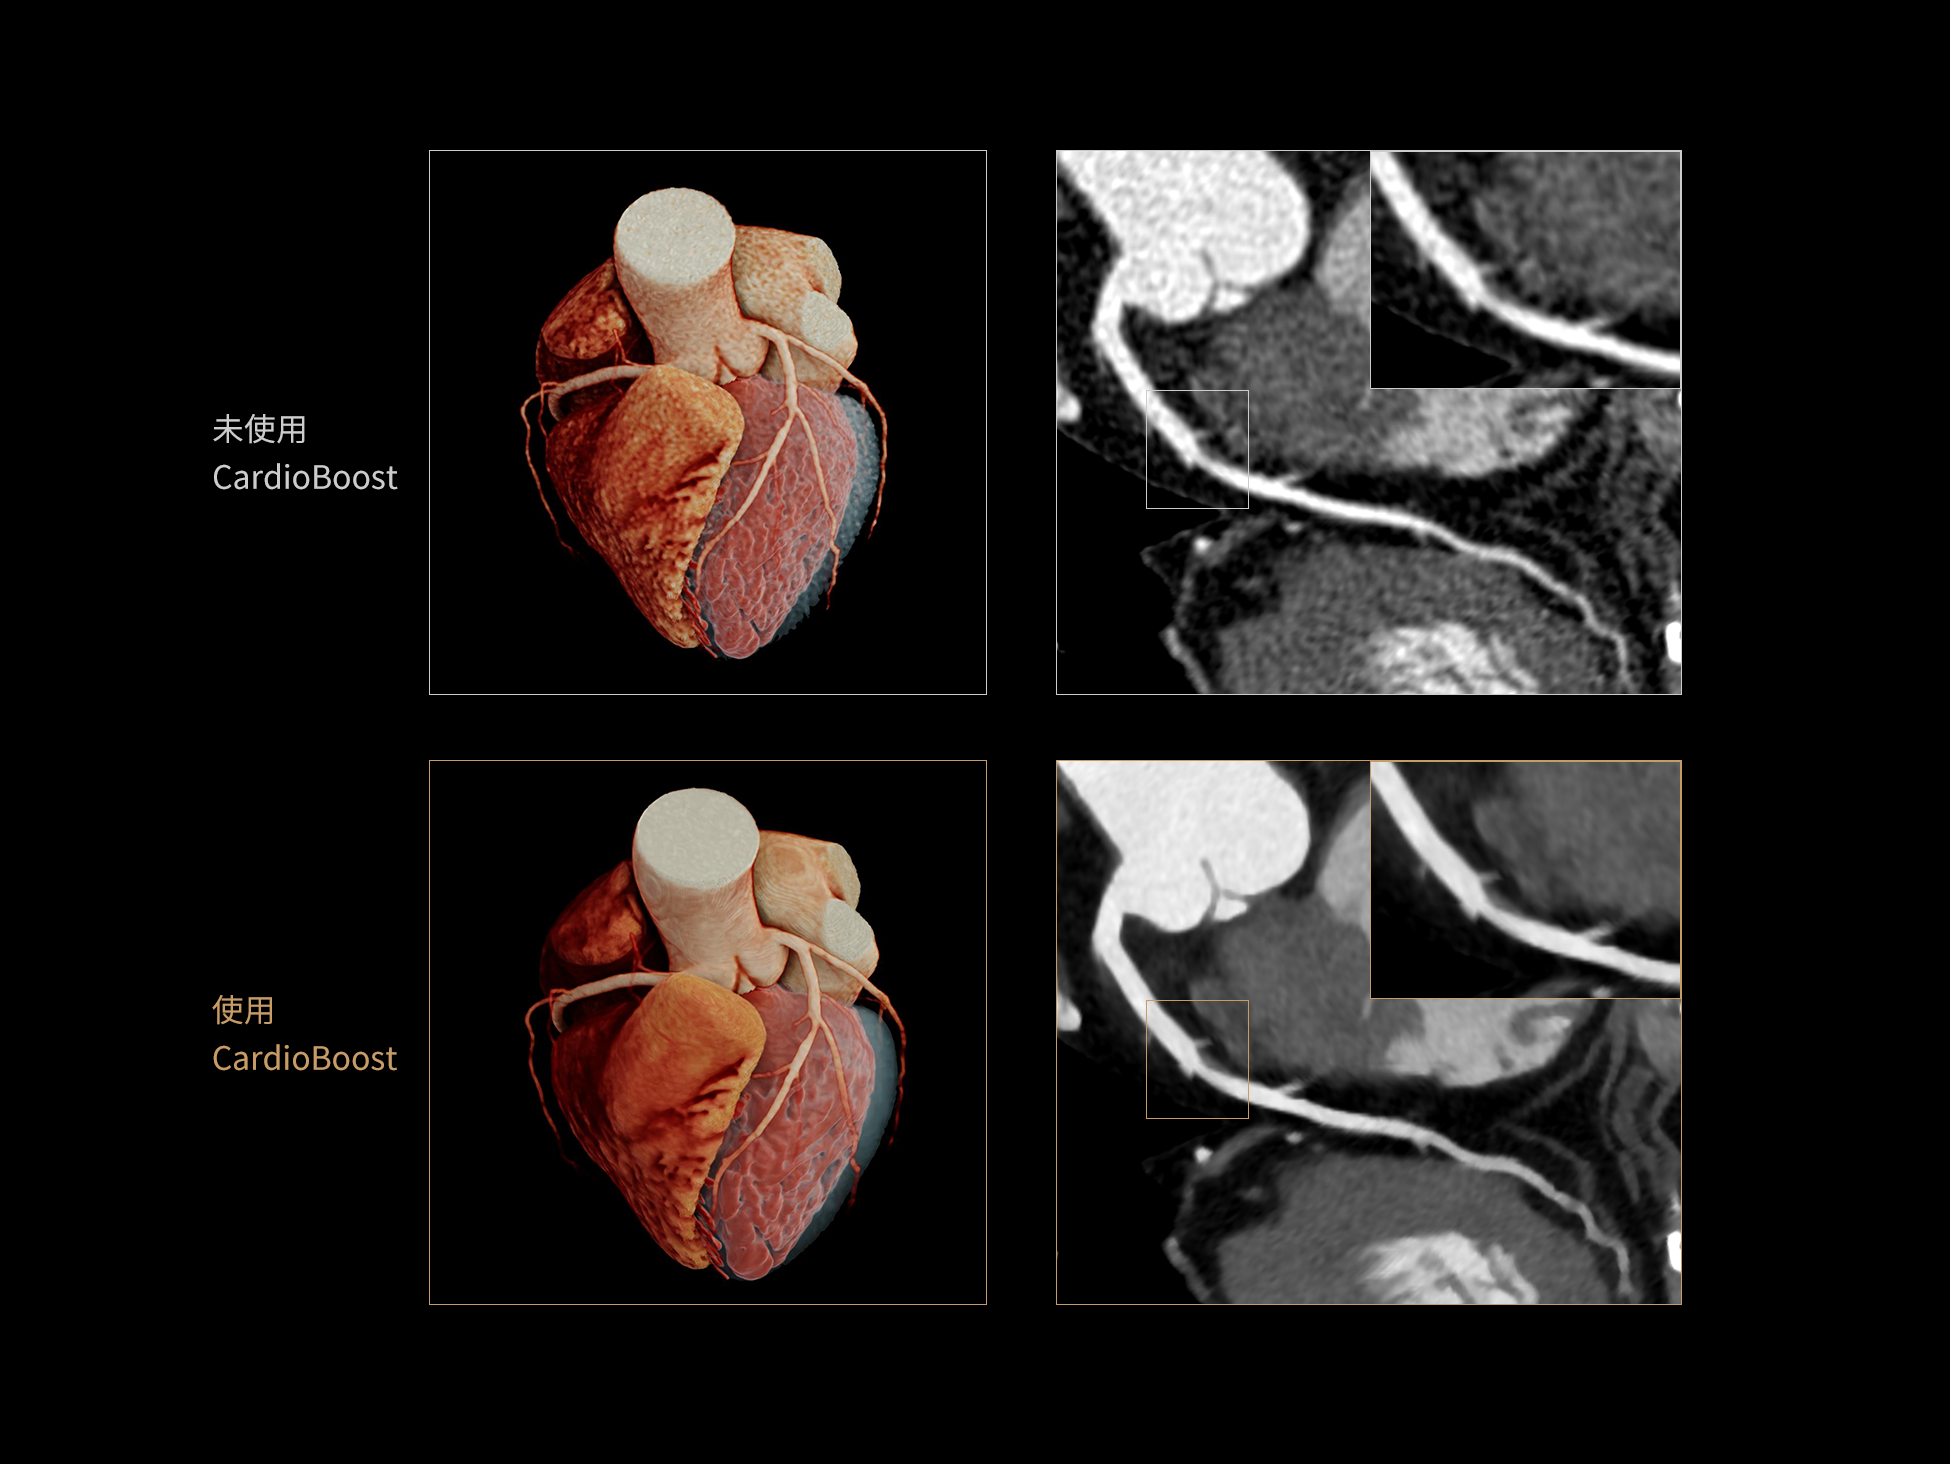

超真实渲染(Hyper Realistic Rendering,HRR)可将医学影像数据转化为高度真实、细节丰富的三维数字可视图像。相比传统VR渲染,HRR在解剖结构与图像细节的还原上更为精准,助力临床直观地理解病灶特征与组织关系,更加适用于术前规划、教学演示及患者沟通。

HRR超真实物理渲染:精准还原解剖细节的三维可视化技术